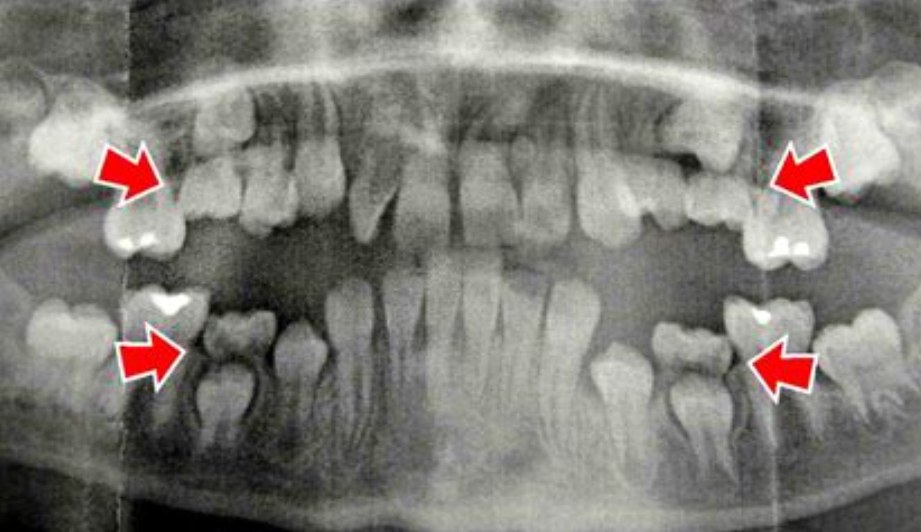

Zęby ankylozowane charakteryzują się brakiem ruchomości, a w przypadku dzieci pozostają w tzw. infrapozycji – są niżej niż pozostałe zęby w łuku. W efekcie mogą prowadzić do: